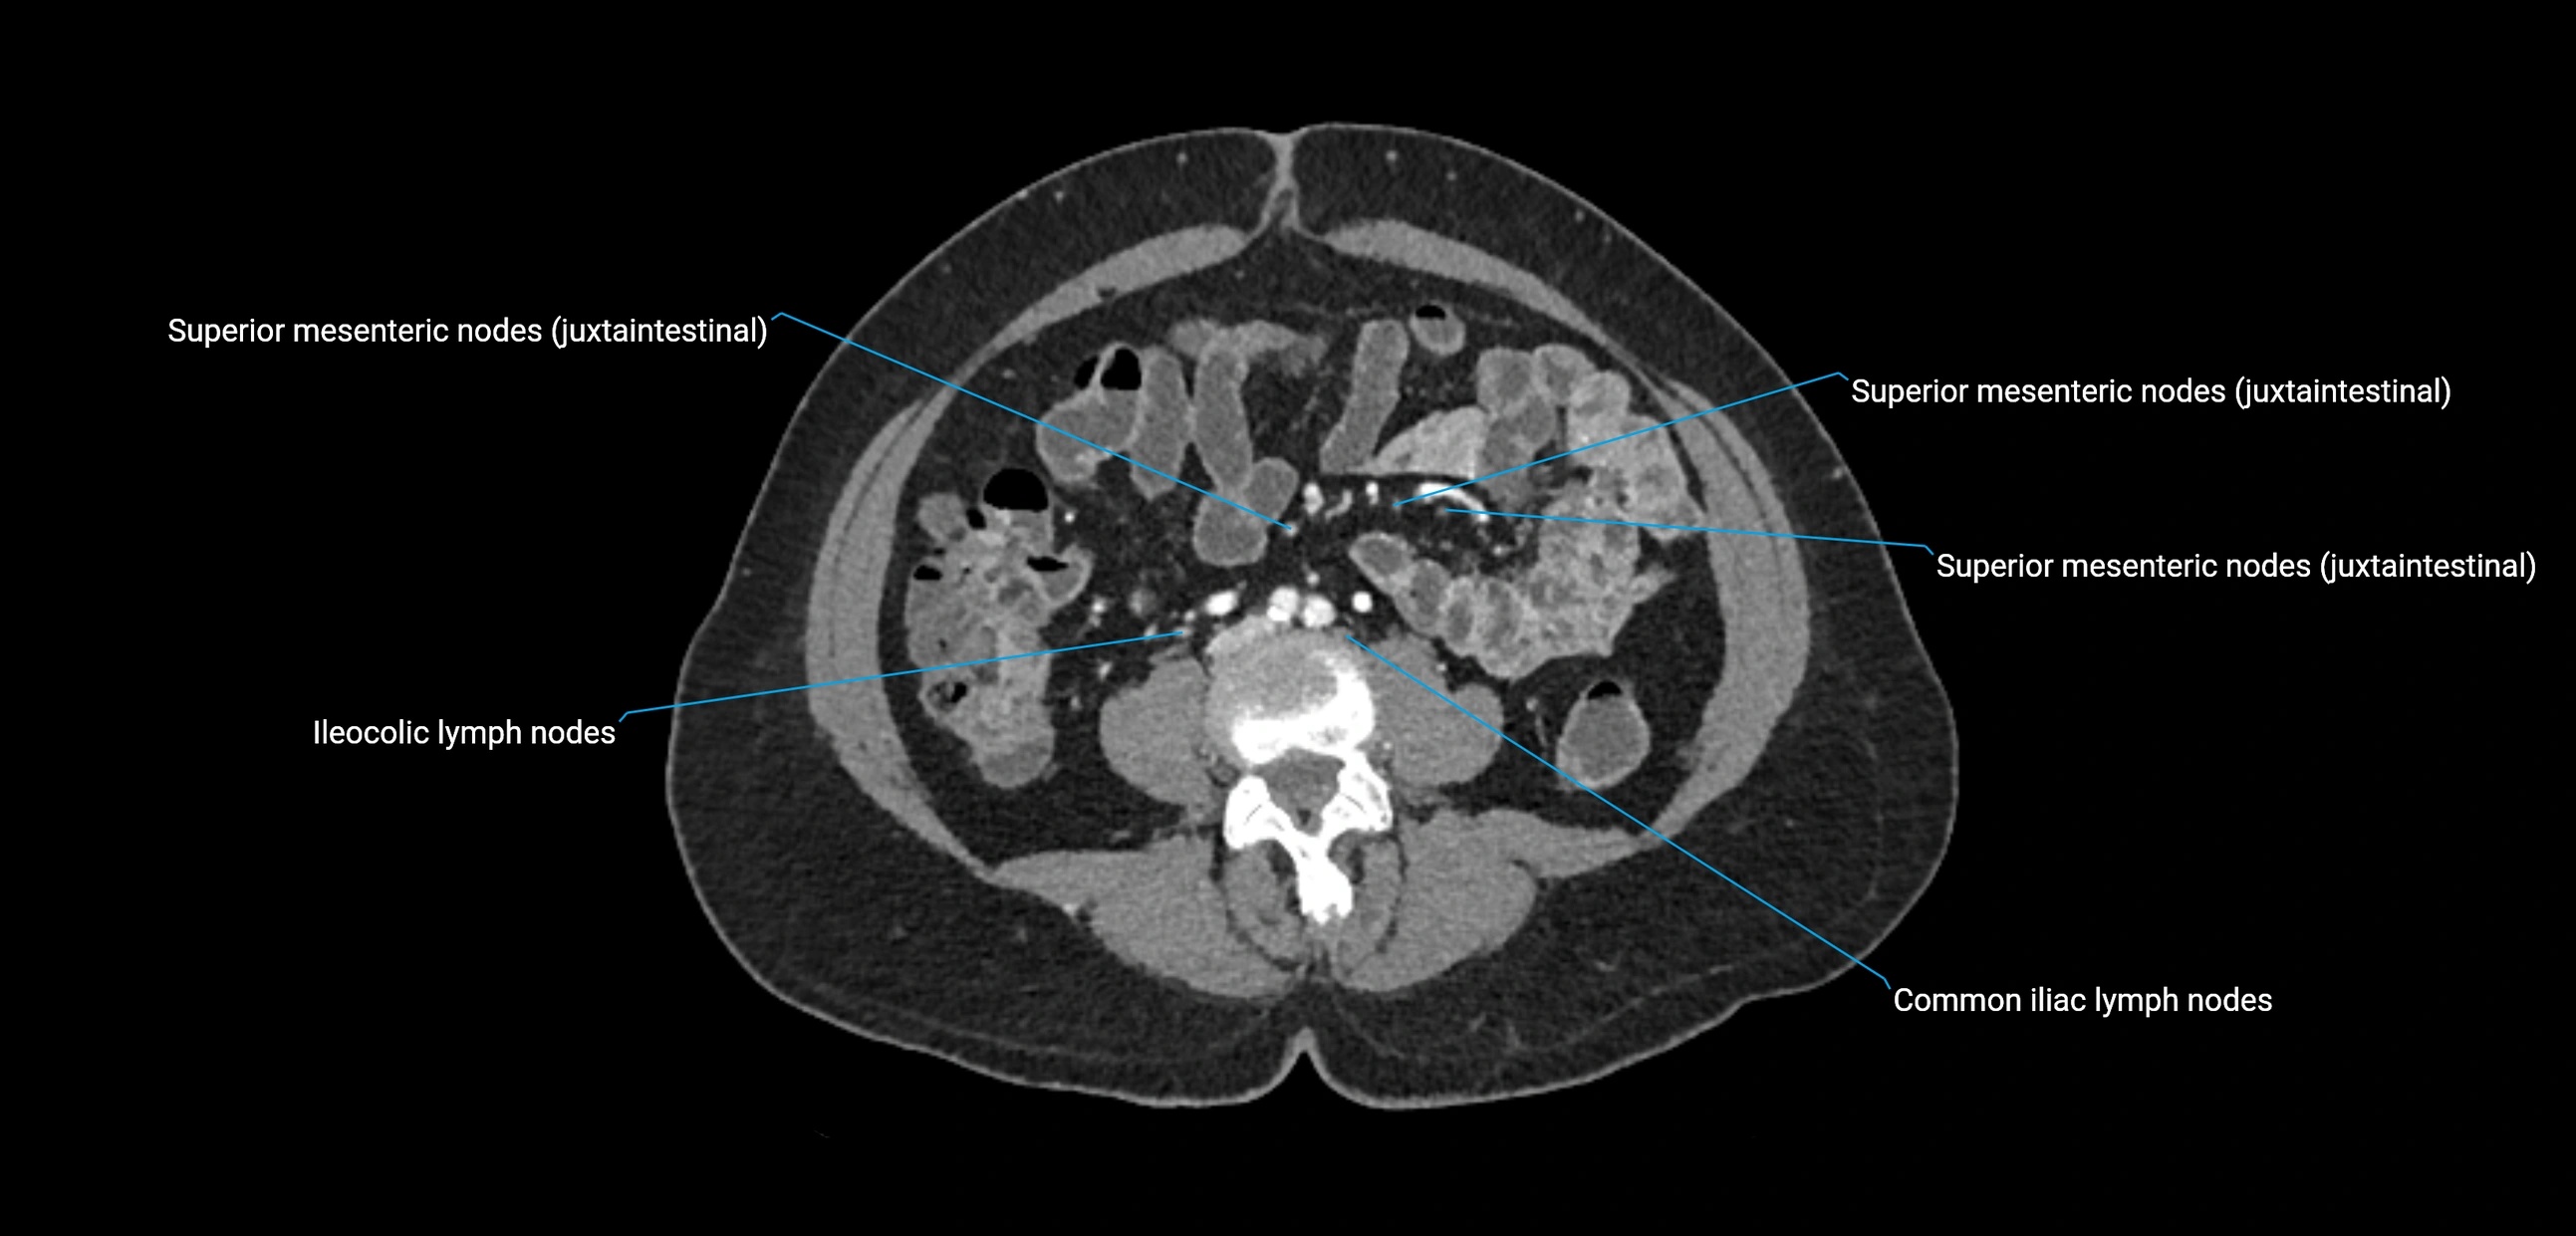

CT Appearance

CT Pre-Contrast:

• Nodes appear as soft-tissue density nodules adjacent to the aorta and IVC

• Calcification may be seen in chronic infections (e.g., tuberculosis)

CT Post-Contrast:

• Normal nodes enhance homogeneously

• Malignant nodes may show heterogeneous enhancement, central necrosis, or conglomerate formation

• Size >1 cm short axis is suspicious, though morphology and distribution are equally important